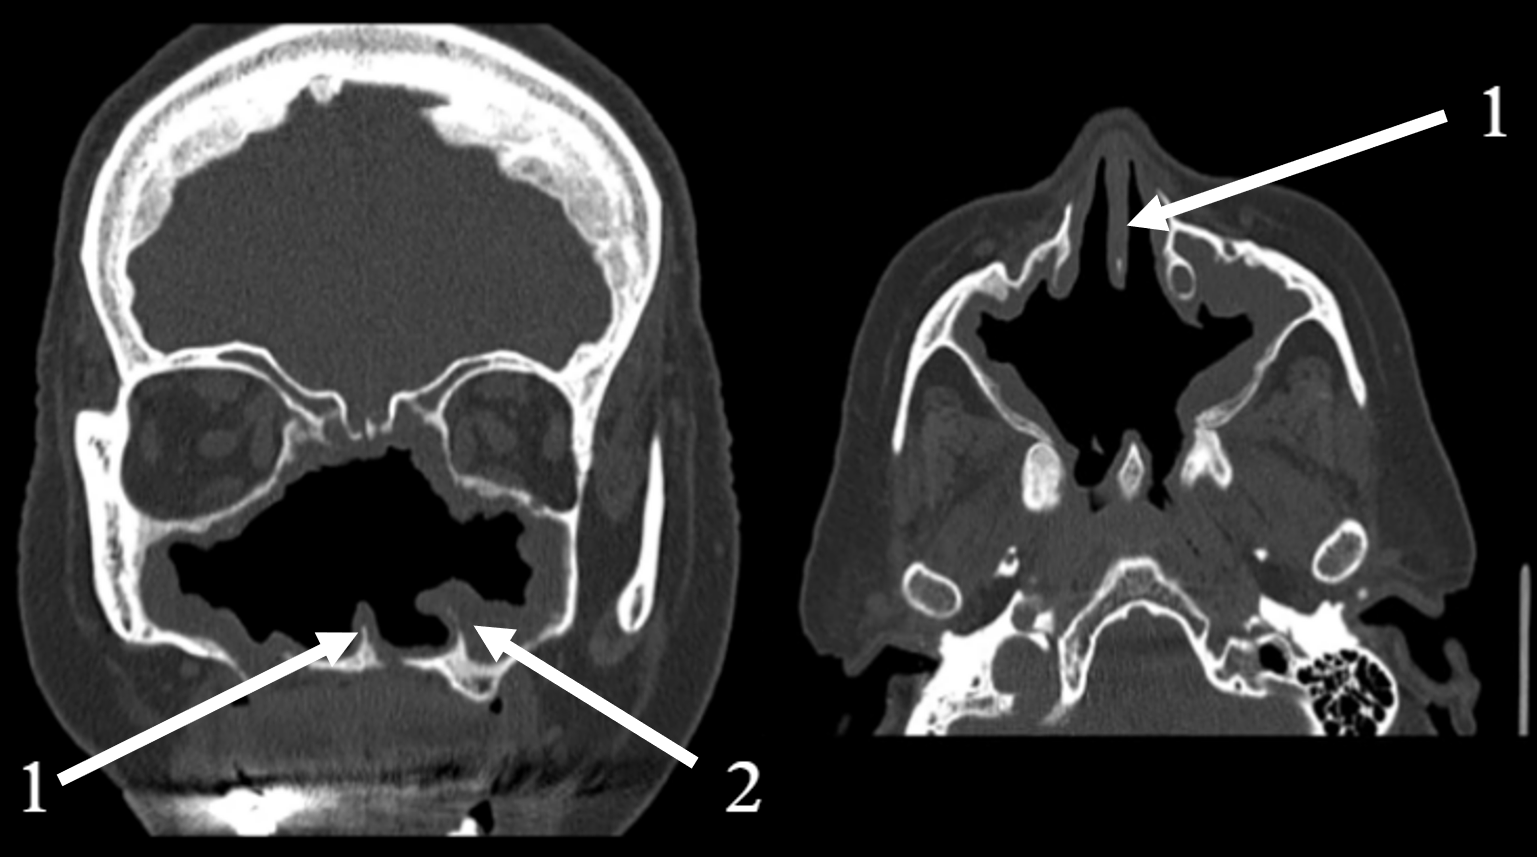

2.2. Clinical and Radiological Findings (2024)

| Late September 2022 | Disease progression | CT scan reveals an “osteolytic process”. A major Polysinusotomy with necrosectomy is performed under general anesthesia, involving extensive removal of necrotic bone and tissue. The second histopathology report confirms the findings of necrotic tissue and bone fragments, with no evidence of fungal invasion or granylomatosis. |

| 2024 | Secondary atrophic rhinitis | Endoscopy, CT scan. Treatment initiation. 3-month follow-up. |